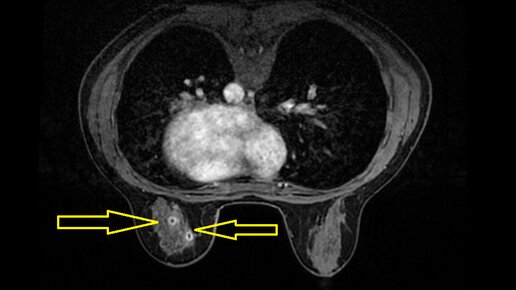

Рак молочной железы in situ, многоочаговость поражения. Клиническое наблюдение.

История пациентки М., 42 года. Более 10 лет назад М. обратила внимание на появление уплотнения в левой молочной железе. При обследовании по месту жительства какие-либо признаки злокачественности выявлены не были.

Около 1 года назад М. обратила внимание на явное увеличение размеров уплотнения.

По месту жительства была предложена небольшая диагностическая операция, М. согласилась. В июле 2023 была выполнена экономная резекция левой молочной железы, форма груди не изменилась, разрез был выполнен аккуратно по краю ареолы (так получаются самые незаметные разрезы), шов наложен косметический...